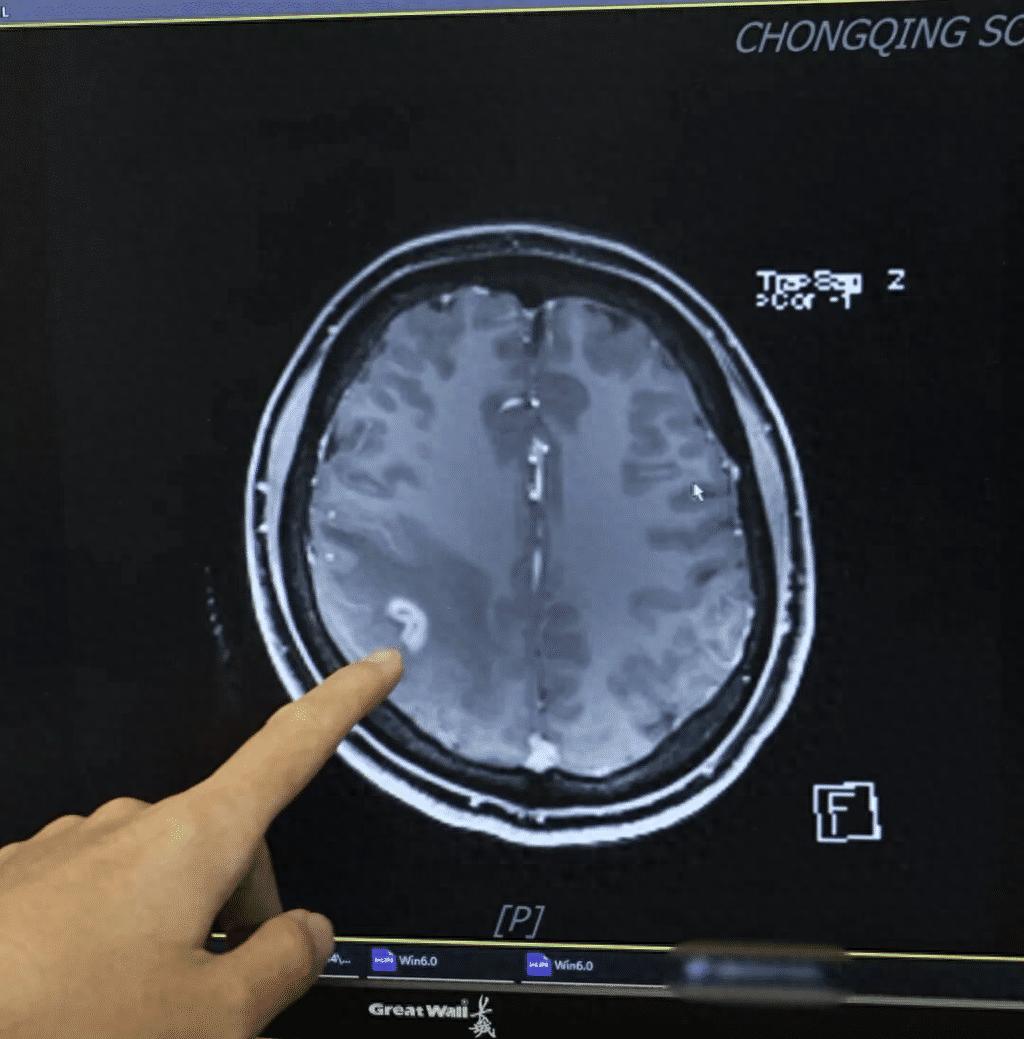

女子多年肢体麻木开颅抓出3厘米活虫!“太感谢了,这么多年终于找到了病因!”3月26日,记者从陆军军医大学西南医院获悉,该院神经内科日前收到了一面来自患者的锦旗,感谢团队帮助她治好了脑部寄生虫感染。患者王女士回忆(化名),5年前她先是突然出现...